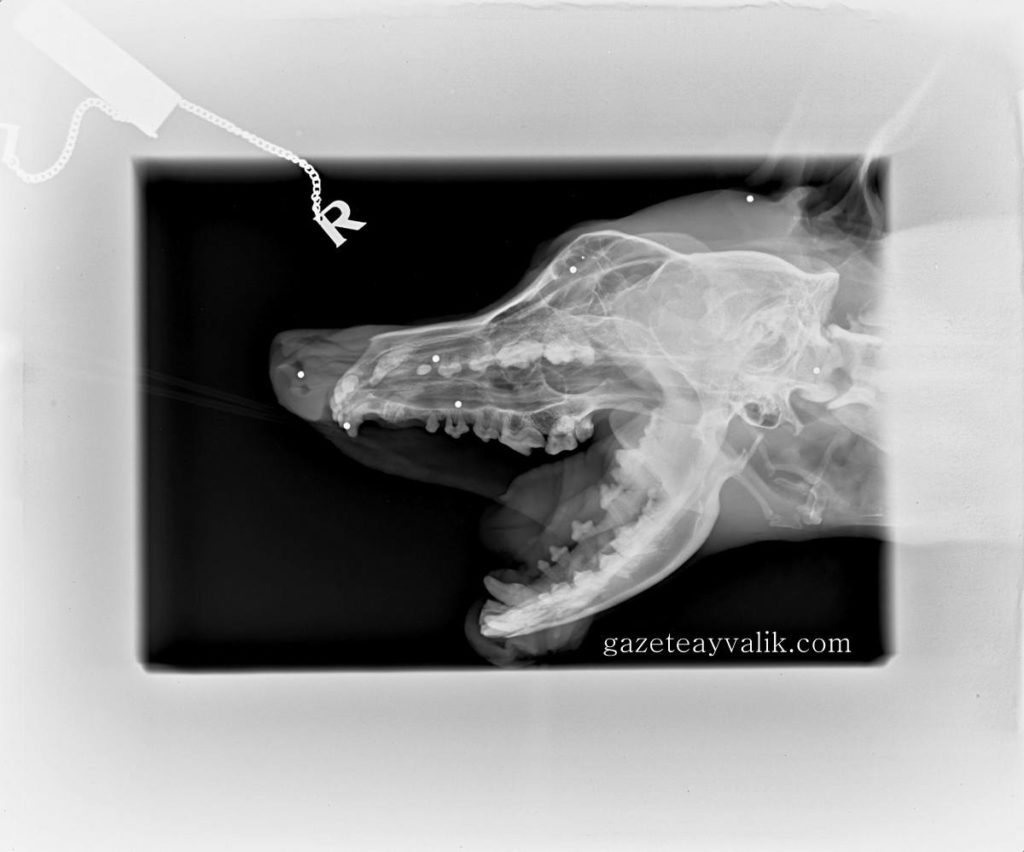

Ayvalık Belediyesi Hayvan Barınağı’nda bakılırken, birkaç kez yazlıkçılar tarafından sahiplenilen, ancak yeniden terk edilen ‘Dük’ isimli köpeği, Altınova Mahallesi sokaklarında yaşarken Almanya’da yaşayan Nurferi Bellisan Ortmann ve Jens Ortmann çifti sahiplendi. 20 yıldır ilçedeki yazlıklarında tatillerini geçiren Ortmann çifti, köpeği dönüşte Almanya’ya götürdü. Altınova’dan 2008 yılında sahiplendikleri ‘İndra’ isimli bir köpekleri daha olan çift, çok sevdikleri Dük’ün dişlerindeki sorun için gittikleri veteriner kliniğinde şoke oldu. Çekilen röntgen filminde, Dük’ün başının çeşitli bölgelerinde 7 saçma olduğu ortaya çıktı.

4 yaşındaki Dük’ün, evlat edinilerek sürekli yeniden sokaklara bırakılma hikayesinin kendisini etkilediğini söyleyen Nurferi Bellisan Ortmann, “Bunlar beni çok etkiledi ve Dük’ü sahiplenmeye karar verdim. Dişleri kötü idi ve tedavi amacıyla röntgen çekildi. Röntgende Dük’ün yüzünde 4 saçma parçası görüldü. Kafatasında toplam 7 saçma saydık. Kontrole gittiğimizde veterinerimizle tekrar konuştuk. Saçma parçalarının isabet ettiği yerler ve çokluğunun önemli olduğunu söyledi. Dük‘ün direk yüzüne ateş edilmiş. Hangi vahşi, hangi amaçla yapmış bilmiyorum. Dük‘ün şimdilik bir sorunu görülmüyor. Saçmalar yumuşak dokuda. Mesela burnunun önündeki, burun çok kanayan bir yapıya sahip olduğu için ameliyatla alınması mümkün değil. Saçmaların zaman içinde yer değiştirmeden zararsız bir şekilde kalmasını diliyoruz. Vücudunun röntgeni çekilmediği için o kısımlarda da var mı bilmiyoruz. Vücuttaki saçma çokluğu ise kurşun zehirlenmesi yaptığından ölümcül oluyor” dedi.